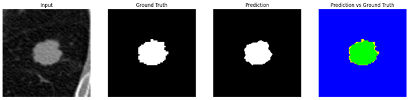

3.4.2. Representative Cases with Segmentation Challenges on the MEF-PN35 Dataset

To complement the quantitative evaluation, we present a set of representative cases from the clinical dataset that exhibited typical segmentation challenges. These cases were selected to reflect diverse morphological characteristics observed in pulmonary nodules, such as spiculated boundaries, small size, vessel adherence, pleural attachment, cavitation, and clear isolation. Rather than aiming for exhaustive categorization, our intent is to highlight a range of practical difficulties encountered in real-world scenarios and to qualitatively assess how different boundary-aware loss functions respond to these variations. Each challenge is labeled (C1) through (C5) in Table 10 and is consistently referenced in the corresponding detailed illustrations that follow.

Following the summary in Table 11, we present detailed visual comparisons for selected representative cases, each corresponding to a specific segmentation challenge. These cases are consistently labeled using the Challenge ID (CID) codes defined in Table 9 to facilitate cross-referencing between the summary and the case illustrations. Each table reports segmentation results across three loss configurations (Sobel, Laplacian, and Hausdorff) using five columns. Loss indicates the boundary loss formulation applied in each case, where Dice loss is combined with a boundary term computed using Sobel, Laplacian, or Hausdorff operators. The Segmentation Result column shows four images side by side: the input CT patch, the manual ground truth, the model prediction, and a color-coded difference map between ground truth and prediction. In this map, green indicates true positives, blue represents true negatives, red corresponds to false positives, and yellow denotes false negatives. The final column, Attention Map, presents Grad-CAM visualizations derived from one of the Adaptive Attention Fusion (AAF) layers in the encoder path. These maps illustrate the spatial focus of the model, with red/yellow regions indicating strong attention and lighter or neutral tones indicating lower activation. All six cases are presented in detail in Table 11, Table 12 and Table 13, providing a comprehensive qualitative analysis of how each loss configuration performs under specific segmentation challenges observed in real clinical data.